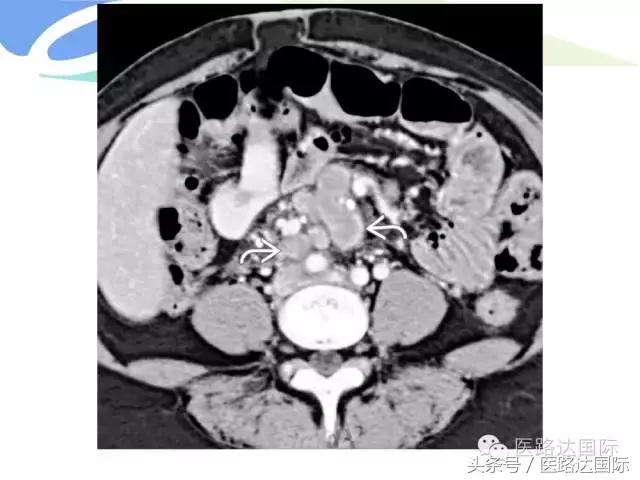

首都医科大学附属北京妇产医院梁宇霆教授从流行病学、临床特点、实验室检查、病理改变、影像学特点及治疗与预后六个方面向我们详细地介绍了女性生殖系统结核;并且着重介绍了子宫输卵管造影(HSG)的作用。在最后,梁教授还向大家介绍了如何鉴别诊断女性生殖系统结核、盆腔炎性病变和卵巢癌。